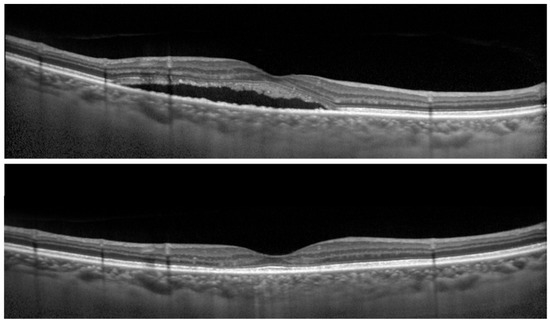

The Spectralis OCT system (Heidelberg Spectralis OCT; Heidelberg Engineering GmbH, Heidelberg, Germany) was used to obtain macular scans. The Spectralis OCT system (Heidelberg Spectralis HRA2; Heidelberg Engineering GmbH) was used for FA and ICGA. Clinical data at pre- and post-treatment were recorded. For Spectralis OCT examinations, average values were obtained for horizontal and vertical line scans through the fovea. At baseline, the central foveal thickness (CFT) was measured from the inner surface of the neurosensory retina to the outer surface of RPE at the fovea (Figure 3). The SRD height was defined as the distance between the outer surface of the sensory retina and inner surface of RPE at the fovea (Figure 3). ONL thickness was measured as the distance between the outer surface of the inner limiting membrane and inner surface of the external limiting membrane (ELM) at the central fovea (Figure 3). Disruption of the ELM layer and the ellipsoid zone (EZ) layer within 500 μm from the fovea was also evaluated. Eyes in which these findings were detected in at least one scan of horizontal and vertical line scans were classified as having the presence of these findings. Since evaluating the EZ layer disruption at baseline was sometimes difficult because of the SRD or elongated photoreceptor OS, we evaluated it only at post-RFPDT.

Horizontal optical coherence tomography images of eyes with central serous chorioretinopathy, the serous retinal detachment (SRD) height, the central foveal thickness (CFT), and the outer nuclear layer (ONL) thickness are shown.

Figure 3. Optical coherence tomographic image of eyes with central serous chorioretinopathy.